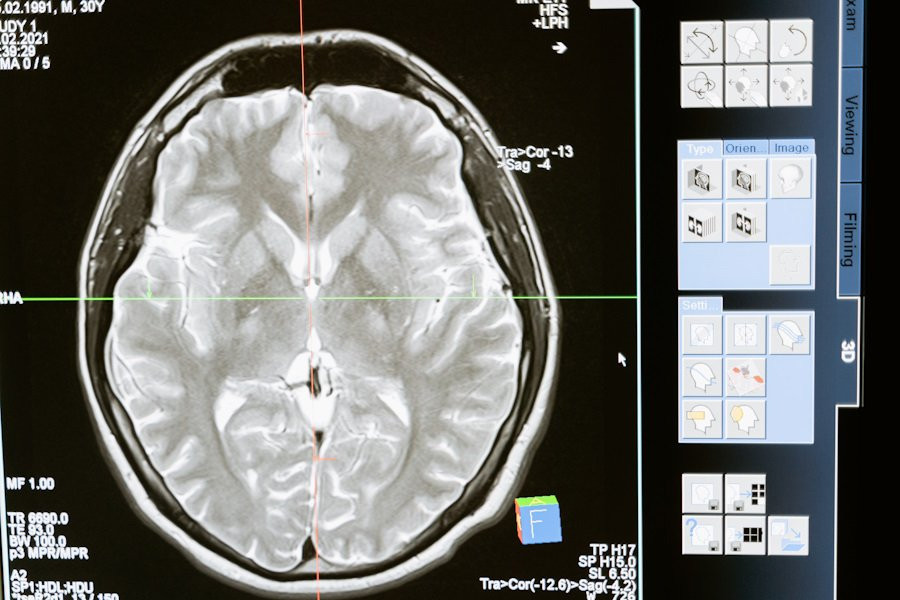

Портал Medical Xpress сообщает, что метаболиты, выделяемые вредными бактериями в кишечнике, могут проникать в мозг, вызывая воспалительные процессы, которые, в свою очередь, способствуют развитию болезни Альцгеймера. Этот процесс особенно остается актуальным с возрастом, поскольку с возрастом ослабевает барьер между кровью и мозгом, что позволяет вредным веществам наносить ущерб нейронам.